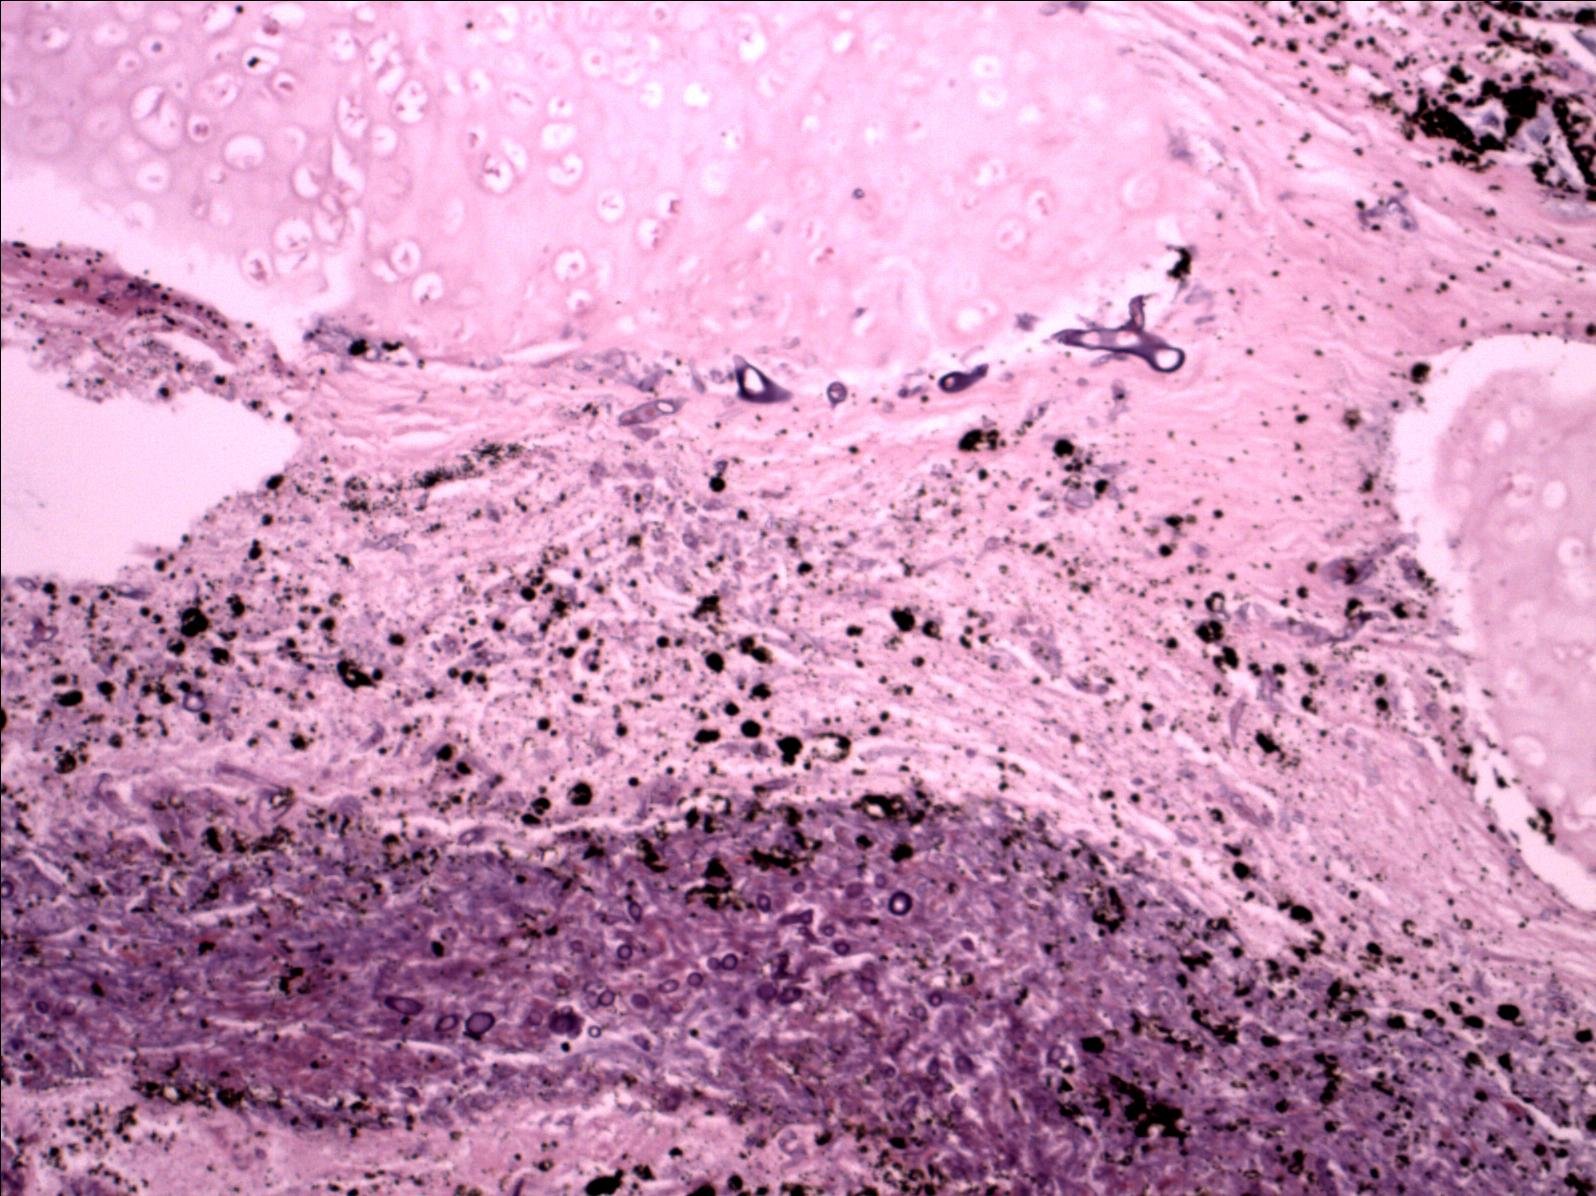

broad, non-septate hyphae seen here are characteristic for mucor

图片尺寸504x331